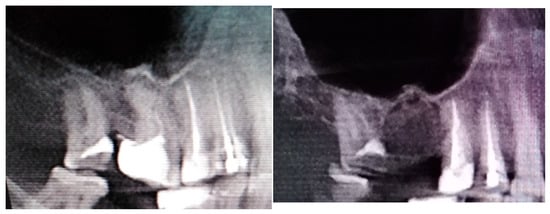

Figure 5. The inappropriate endodontic treatment of the upper second molar led to its inner root resorption, forming of granulation tissue, and the co-incidence of the right maxillary sinus retention cyst. The inflammation and granulation tissues, adjacent teeth, and bone were scheduled for removal. Because of combining wound debridement, cyst, and teeth removal, from the same approach, few different procedures were made. Wound debridement and removal of granulation and inflamed tissues, along with some bone, were scheduled. Because of the presence of oro-antral communication, resulting from the loss of wast bone tissue, the Bihat fat pad was used to close the communication and suture the wound in two layers. The blue, green, and red reference lines are related to CBCT evaluation in axial, sagittal, and coronal views respectively.